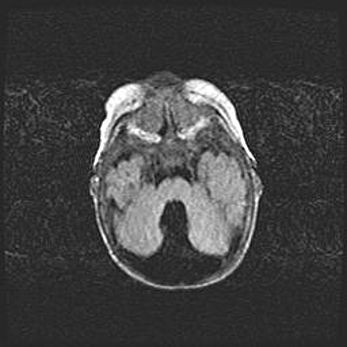

Мальформация Денди-Уокера. Киста задней черепной ямки.

Агенезия мозолистого тела.

Возраст: 2,5 месяца

Вес: 2420 г

Пол: женский

Окружность головы: 37 см

Срок гестации: 32 недели

Мальформация Денди—Уокера — редкий вид патологии ЦНС, представляющий собой врожденный порок развития каудального отдела ствола и червя мозжечка, ведущий к неполному раскрытию срединной (Мажанди) и латеральных (Лушка) апертур IV желудочка мозга. Для этогно синдрома характерна триада симптомов: гипотрофия червя мозжечка и/или полушарий мозжечка, кисты задней черепной ямки, гидроцефалия различной степени. В 70% случаев порок сочетается и с другими аномалиями головного мозга, в частности с агенезией мозолистого тела.